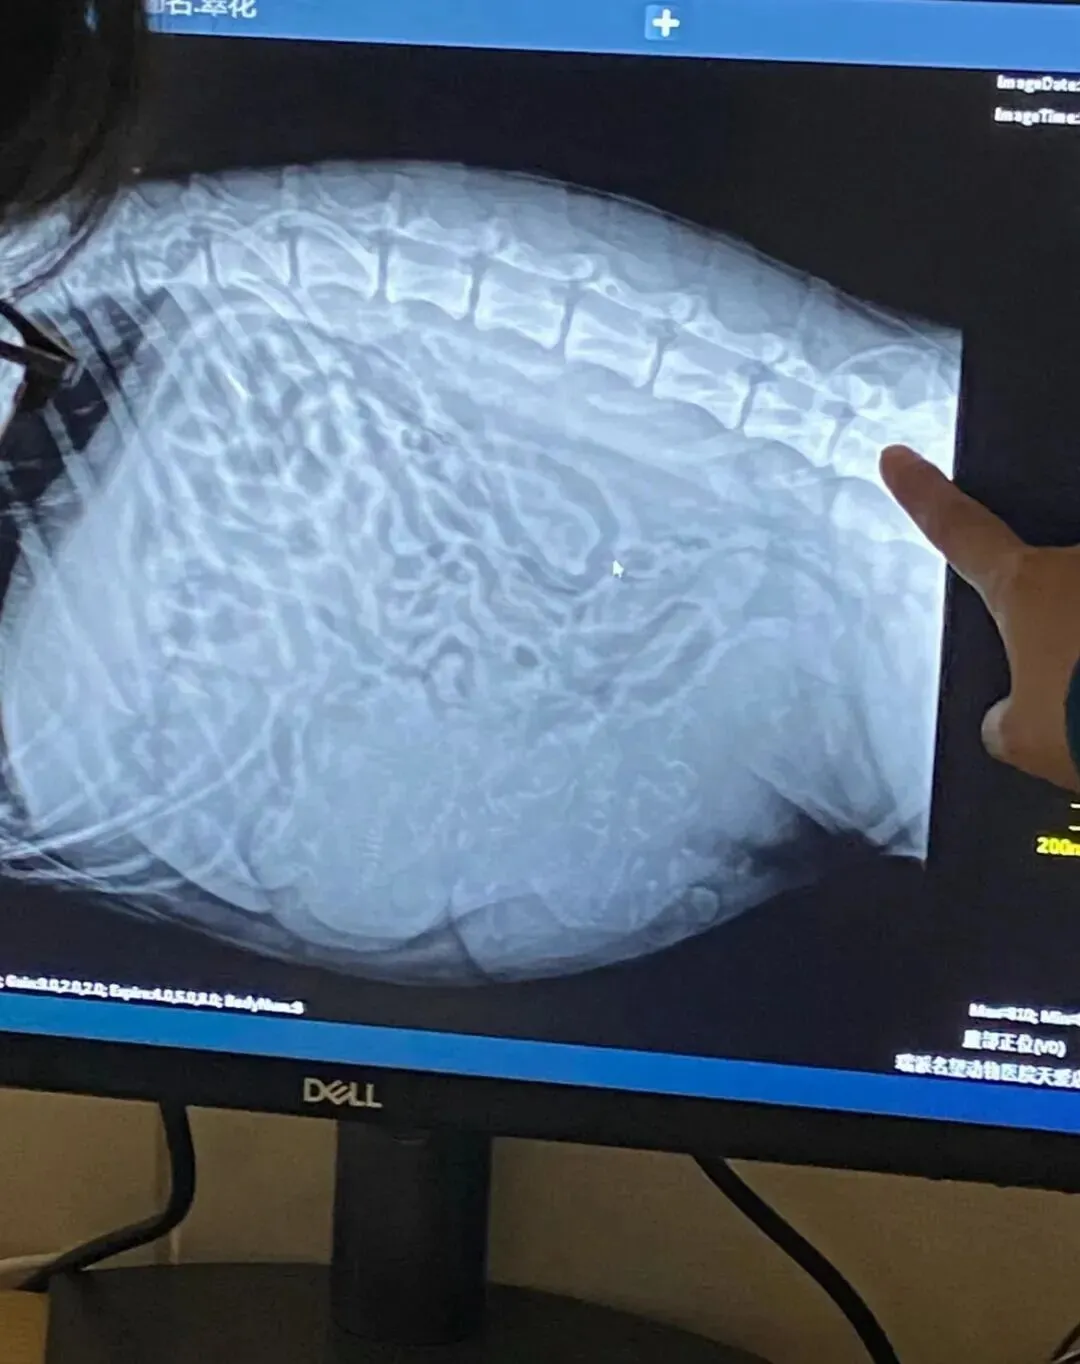

后来到了预产期前 , 带去医院做检查 , 医生看完B超说 , 至少五只 , 快了 , 回家等着吧

五只啊 , 当时就觉得够多了对吧 , 毕竟德牧和秋田混血 , 体型也不小 , 五只已经是大工程了

加上之前的两只 , 一共十只宝宝 , 医生说的五只直接翻了个倍 , 这肚子也太能装了吧?